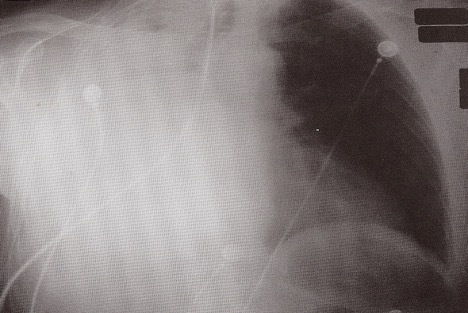

What features are seen on this CXR? What is the likely diagnosis?

Lung markings absent on left

Pneumothorax